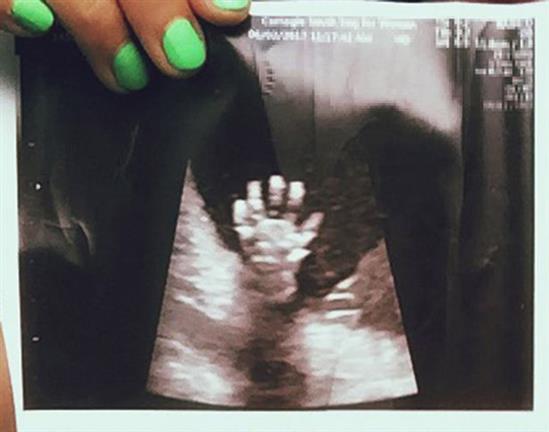

Một bà mẹ mang thai 20 tuần đã kinh ngạc khi xem ảnh siêu âm và thấy con giơ 5 ngón tay như để “high-five” (đập tay) với mẹ.

Libby cầm bức ảnh siêu âm lúc mang thai 20 tuần.

Trong lần siêu âm ở tuần thứ 20, cặp đôi vô cùng ngạc nhiên khi nhìn thấy con gái giơ cả bàn tay lên, xòe ra 5 ngón. Cặp vợ chồng đăng bức ảnh này lên mạng xã hội và nó lan truyền nhanh chóng, theo Mirror.

Bé gái giơ cả bàn tay lên, xòe ra 5 ngón.